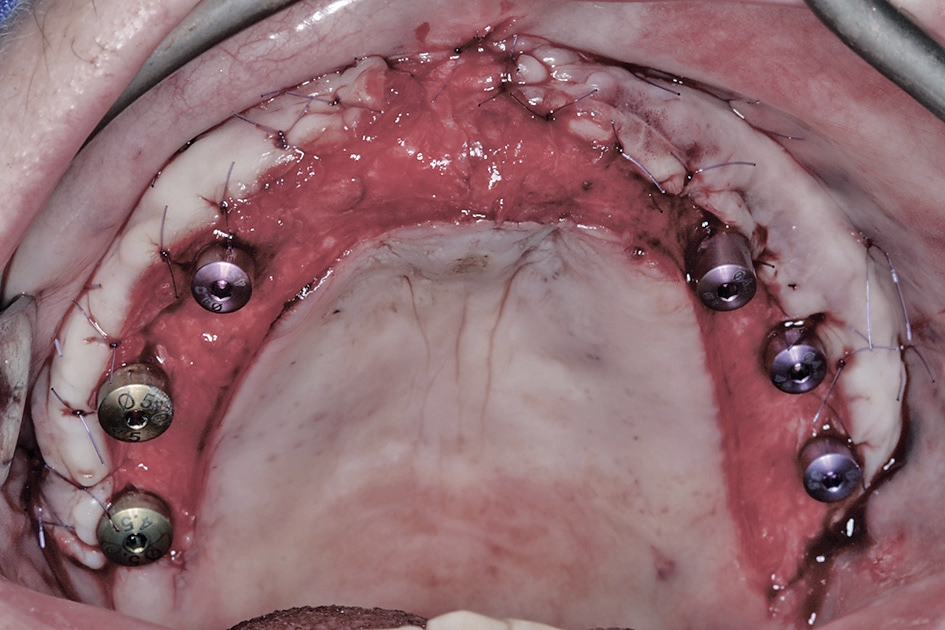

Den dritten und letzten chirurgischen Behandlungsschritt stellte die Freilegung der Implantate und Versorgung mit Gingivaformern dar. In diesem Fall wurde ein apikaler Verschiebelappen [5] präpariert, um den ursprünglichen anatomischen Verlauf der mukogingivalen Grenze wieder herzustellen und einstrahlende Bänder im periimplantären Bereich zu vermeiden (Abb. 19 bis 21). Nach 14 Tagen zum Zeitpunkt der Nahtentfernung sieht das Gewebe gewöhnlicherweise noch etwas „wild“ aus, weswegen man mit der Abformung besser 3 bis 4 Wochen nach der Freilegung warten sollte.